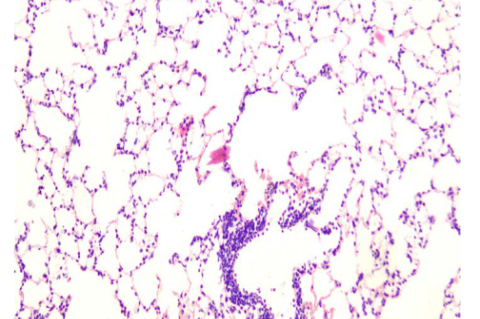

Histopathology of lung tissue consisting of alveoli and bronchioles

Acute Toxicity Study of the Crude Aqueous Extract of Tribulus terrestris Dried Fruit with Potential Diuretic Effect